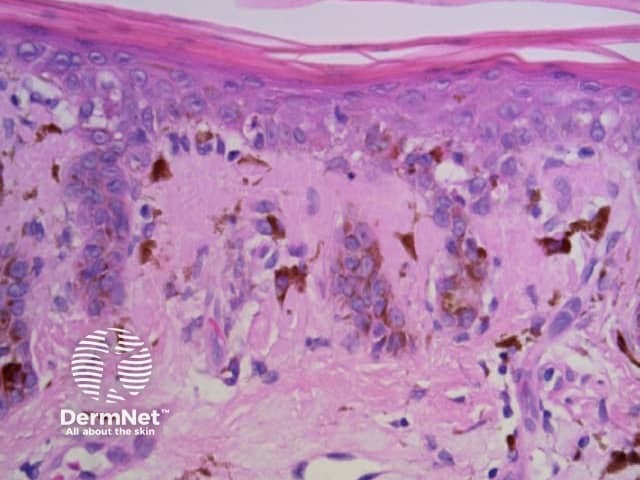

Black dots result either from pagetoid pigmented melanocytes or free pigment within the stratum corneum. Brown dots reflect either small nests of melanocytes in the basal epidermis, focal pigmented keratinocytic proliferation, as seen in some forearm solar lentigines, or superficial dermal haemosiderin deposition. Grey dots are due to melanin pigment within the papillary dermis, either free, in small nests of melanocytes or, more commonly, in melanophages. Blue dots reprresent deeper dermal melanin. The differential diagnosis of dots on dermatoscopy is shown in Figure 34.

Dots are small enough to have no discernable shape at the magnification provided by a dermatoscope. They represent melanin, or occasionally haemosiderin, with the colour depending on the level of the pigment within the skin in the case of melanin. Dots may be black (superficial epidermal melanin), brown (basal epidermal melanin or superficial dermal haemosiderin), grey (papillary dermal melanin) or blue (reticular dermal melanin). They are usually present in association with another pattern. Brown or grey dots are occasionally found without another pattern (Figures 34-36). Red dots, representing a vascular pattern, are discussed later.